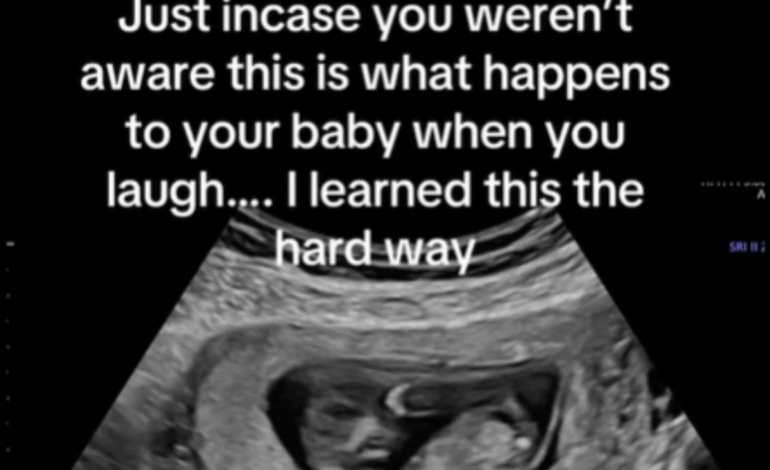

Ross posted the video with a caption stating, “Just in case you weren’t aware, this is what happens to your baby when you laugh… I learned this the hard way.” In an interview with Newsweek, she explained that she was feeling anxious during her ultrasound at 11 weeks of pregnancy. “Not seeing your baby in a couple of weeks can always be a little nerve-racking,” she said.

During the ultrasound, the sonographer noted that the baby appeared to have hiccups, prompting Ross to laugh. “While it looks super violent in the video, babies actually love it when you laugh,” she clarified. The release of serotonin during laughter is believed to calm the baby, despite the visible jostling. “They have so much padding and fluid in there that they are totally fine,” Ross reassured viewers.

The humorous nature of the situation made Ross laugh even harder upon seeing the screen. “I had never seen that before and it was actually the funniest thing I’d ever seen,” she recounted. The sonographer’s lighthearted remark, calling the movement an “EARTHQUAKE,” contributed to the overall amusement and eased any lingering concerns Ross had about the baby’s well-being.